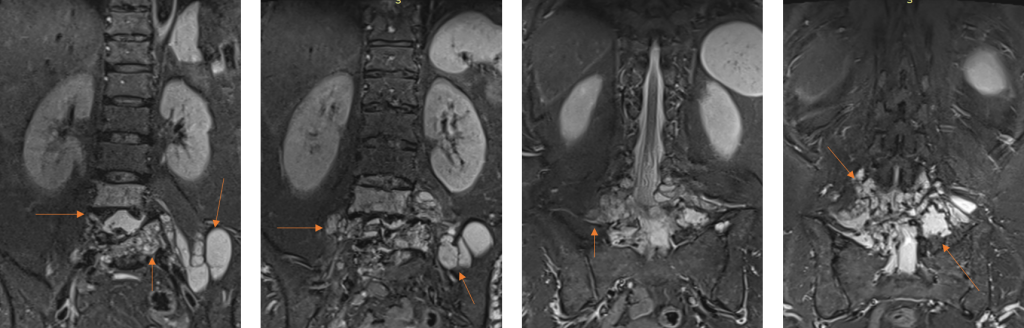

Figura 2: Achiziţie în plan coronal în ponderaţie T2 cu saturaţia grăsimii prin inversie-recuperare

Figura 3: Reconstrucţie în plan oblic-axial din achiziţie 3D în ecou de gradient – ponderaţie T2.